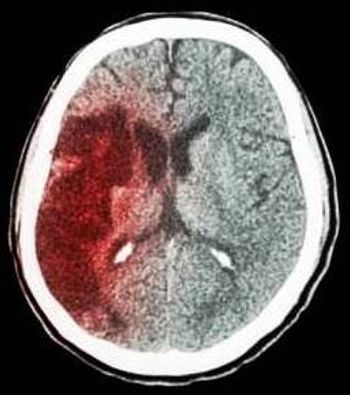

Cancer may be an under-appreciated, but common risk factor for stroke, which is most common the first month after cancer diagnosis.